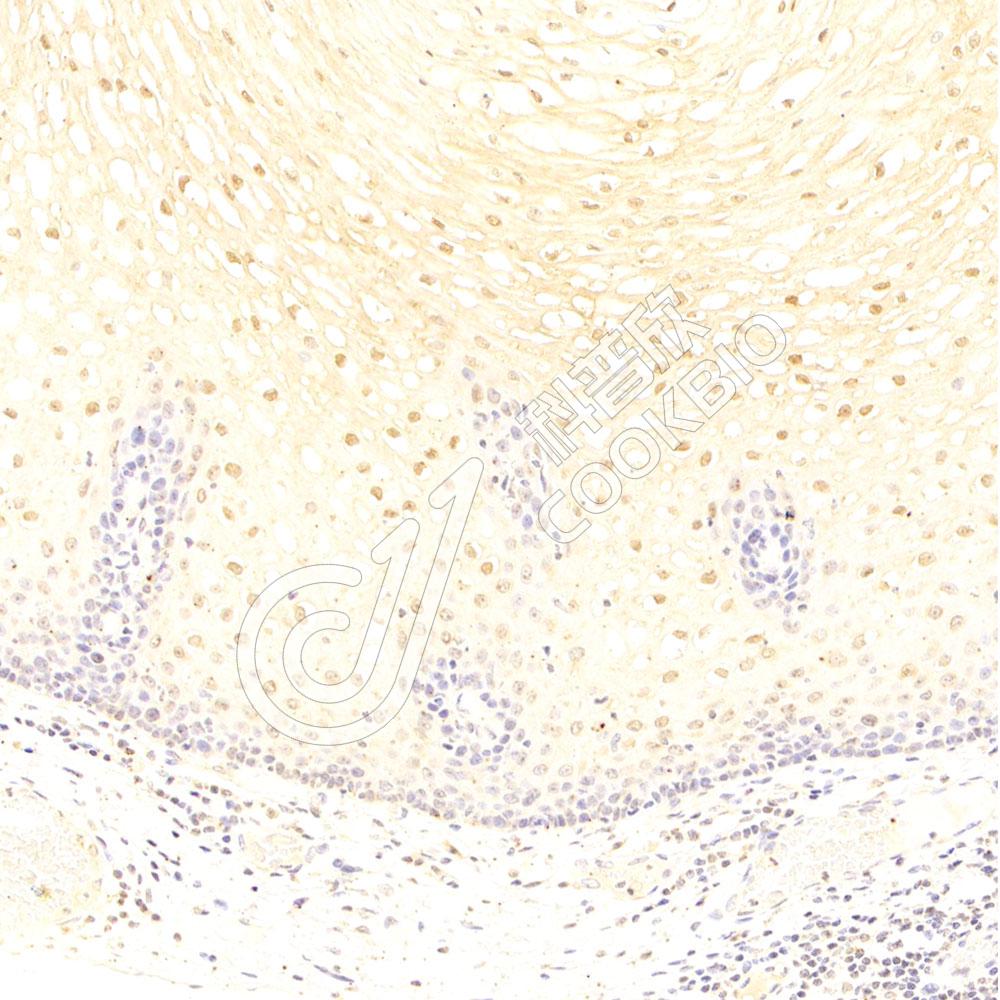

IHC检测IL-2 Receptor alpha蛋白(货号 K134836).

样品: 小鼠脾, 4%多聚甲醛 (货号KSG1101) 固定12-24小时.

抗原修复: 柠檬酸抗原修复液(干粉, pH 6.0) (KSG1201), 98℃, 20分钟.

—抗: 1: 600稀释, 4℃ 孵育过夜.

二抗: S-vision免疫组化多聚二抗(山羊抗兔),即用型 (货号KB3906), 室温孵育20分钟.